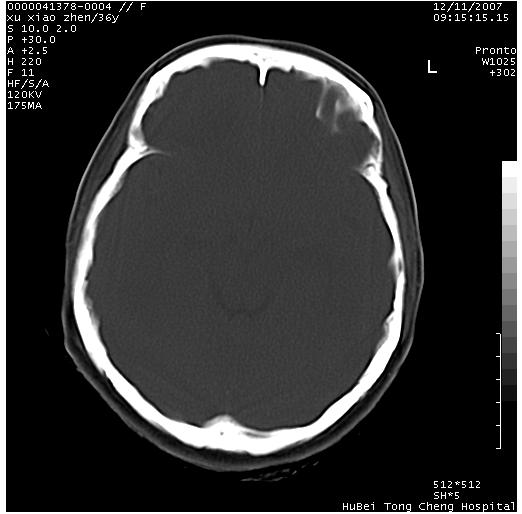

以下是引用wzr在2007-12-12 18:58:00的发言:[br]以脑白质受累,脑肿胀明显,脑室变窄,多考虑炎性改变,建议进一步ce或mri明确.

以下是引用wqs571018在2007-12-12 19:48:00的发言:[br]脑白质受累,脑肿胀明显,脑室变窄,多考虑炎性改变,脑膜炎可能性大;建议mri明确.。